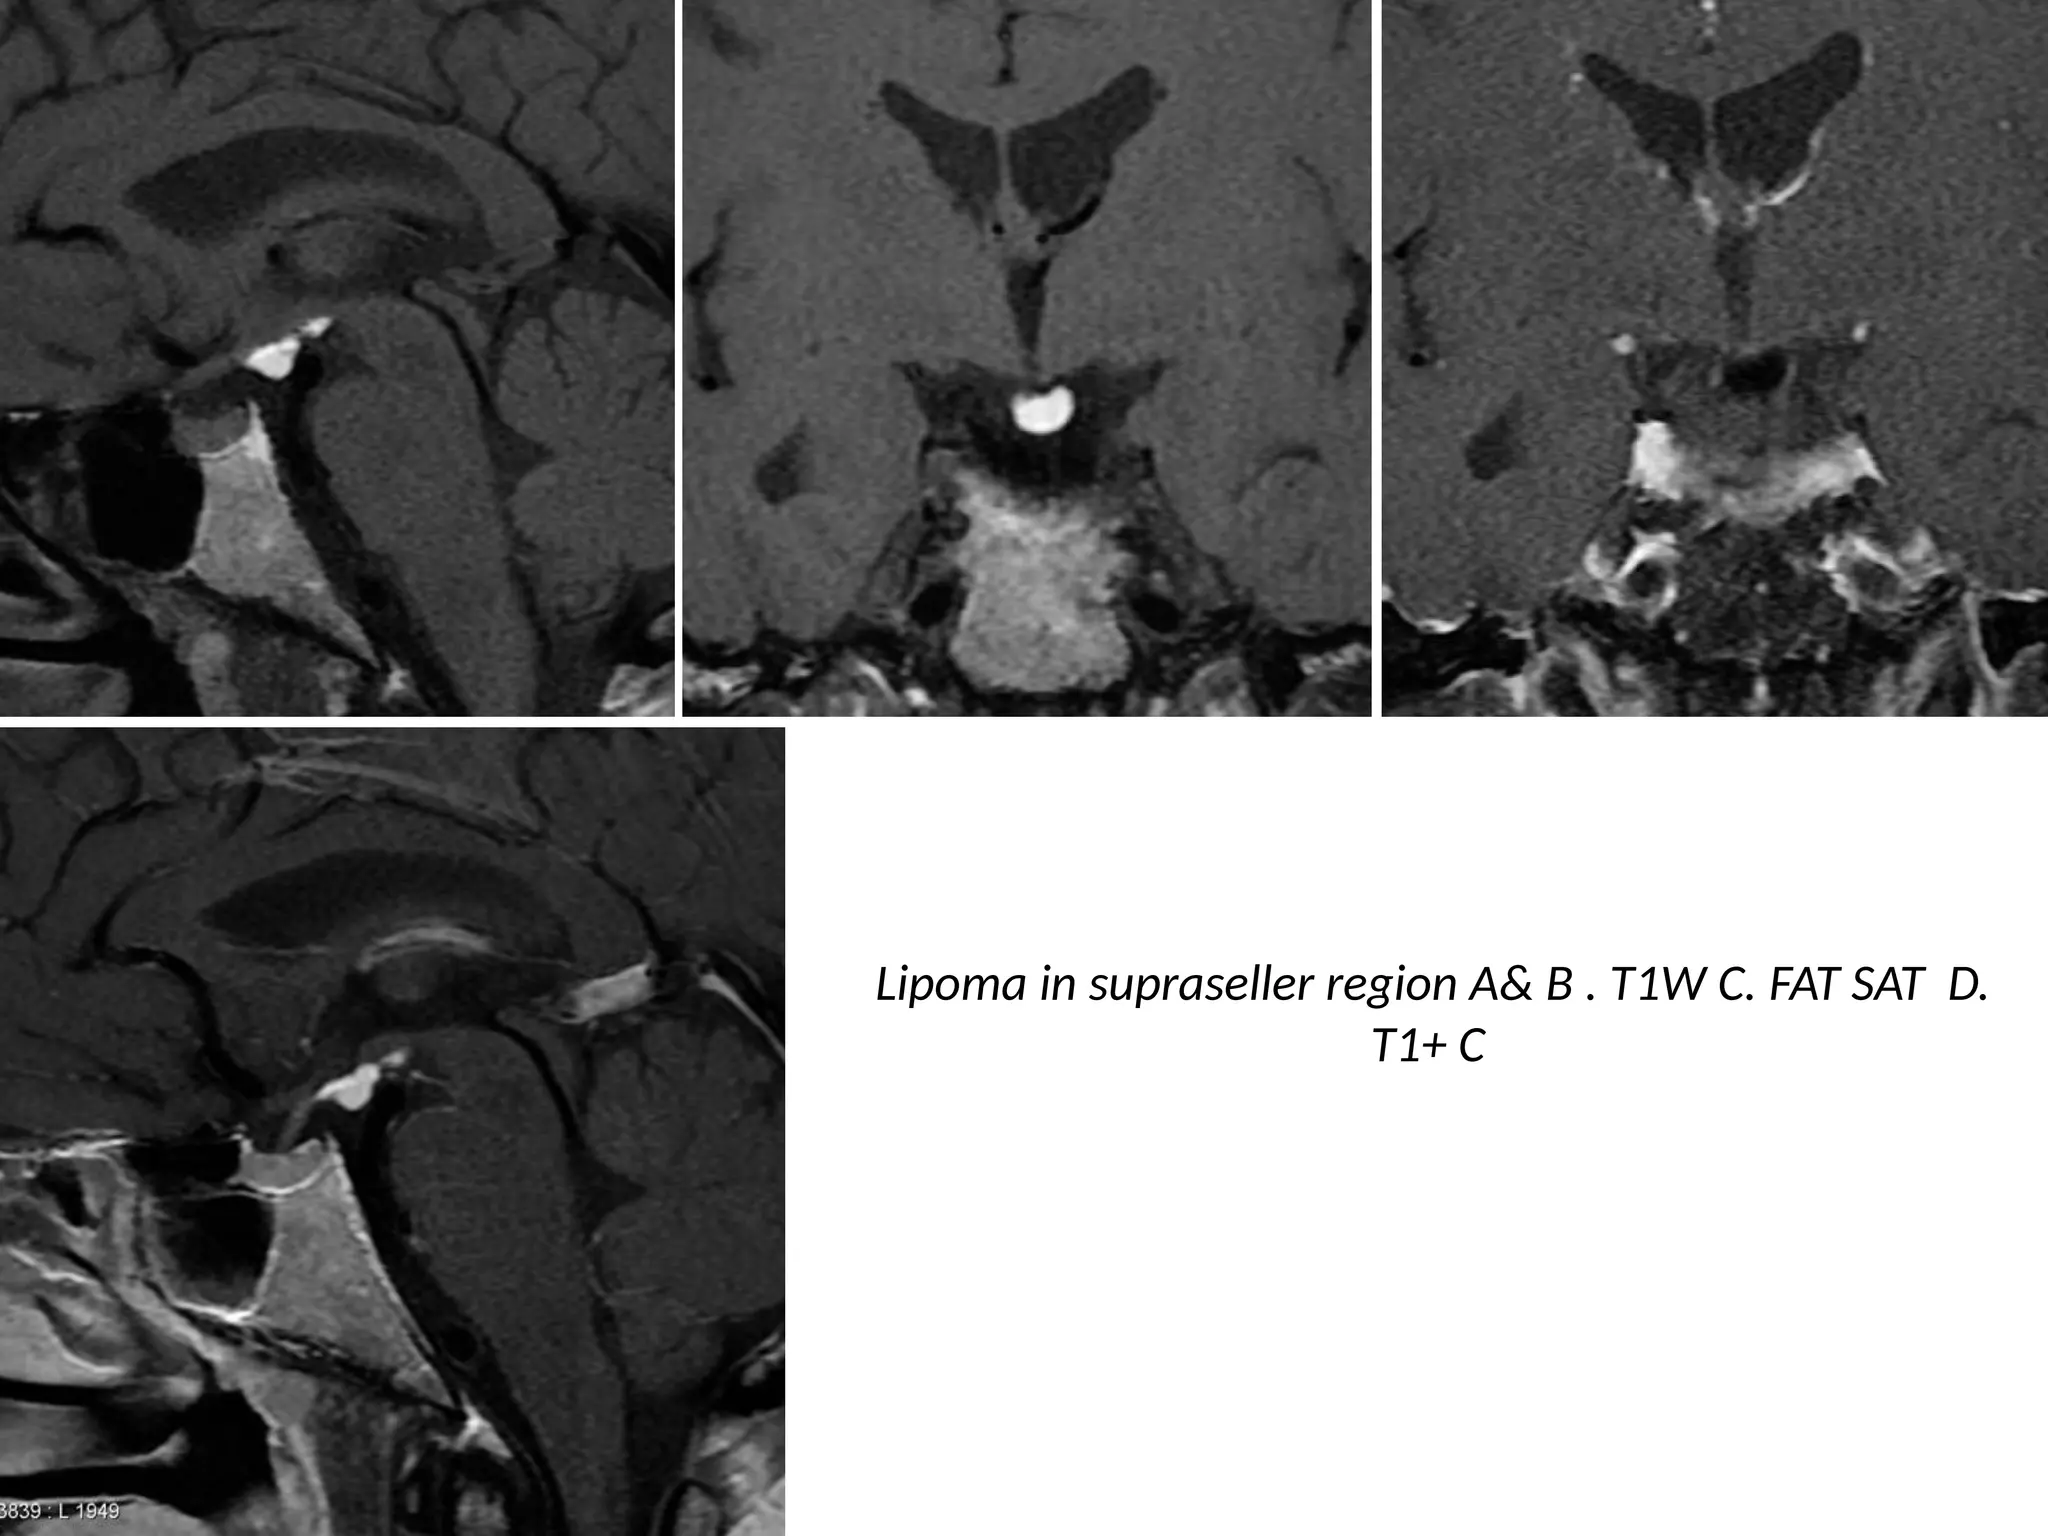

Fat - Calcification - Cyst

• Fat has a low density on CT (- 100HU).

• On MR, fat has a high signal intensity on both T1- and T2WI.

• On sequences with fat suppression fat can be differentiated from high

signal caused by Subacute hematoma, melanin, slow flow etc.

• Fat within a tumor is seen in

– Lipoma,

– Dermoid cysts and

– Teratoma

Lipoma in supraseller region A& B . T1W C. FAT SAT D.

T1+ C

• Fat withina tumor is seen in – Lipoma, – Dermoid cysts and – Teratoma • Some tumors can have a high density on CT. • This is typically seen in lymphoma, colloid cyst and PNET-MB (medulloblastoma).

Lipoma in suprasellerregion A& B . T1W C. FAT SAT D. T1+ C